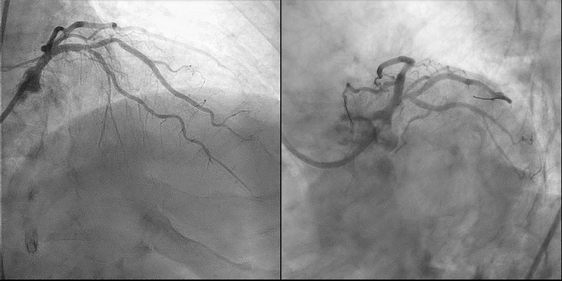

患者急诊介入术后部分影像学资料

随后,手术组迅速调整手术策略,果断使用常用于慢性闭塞病变的Fielder XT-R导引钢丝及Kaneka双腔微导管。“经葛雷教授轻柔的操作,顺利将Fielder XT-R导引钢丝通过最狭窄的部位,顺利送至前降支的远端。”德达医院心内科主任李延林表示,相对常规导引钢丝,Fielder XT-R有两个优势:一是头端非常软,二是带有亲水涂层。